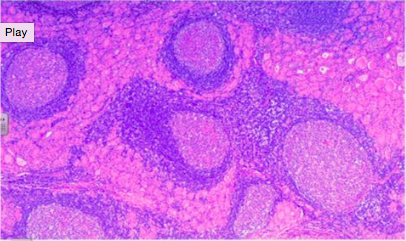

What is this? Describe the prominent histologic features.

Hashimoto’s thyroiditis

NOTE: In all variants of Hashimoto’s, the patient will start out hyperthyroidic and then will become hypothyroid in the long term AND the goiter will be PAINLESS